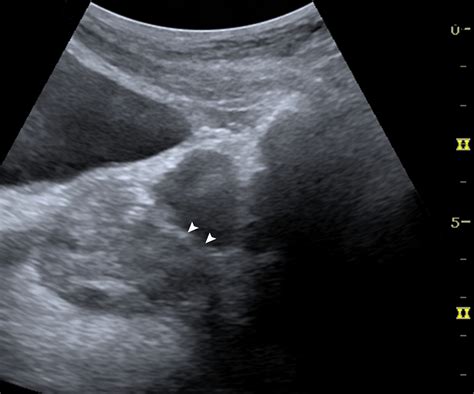

• space of retzius on ultrasound